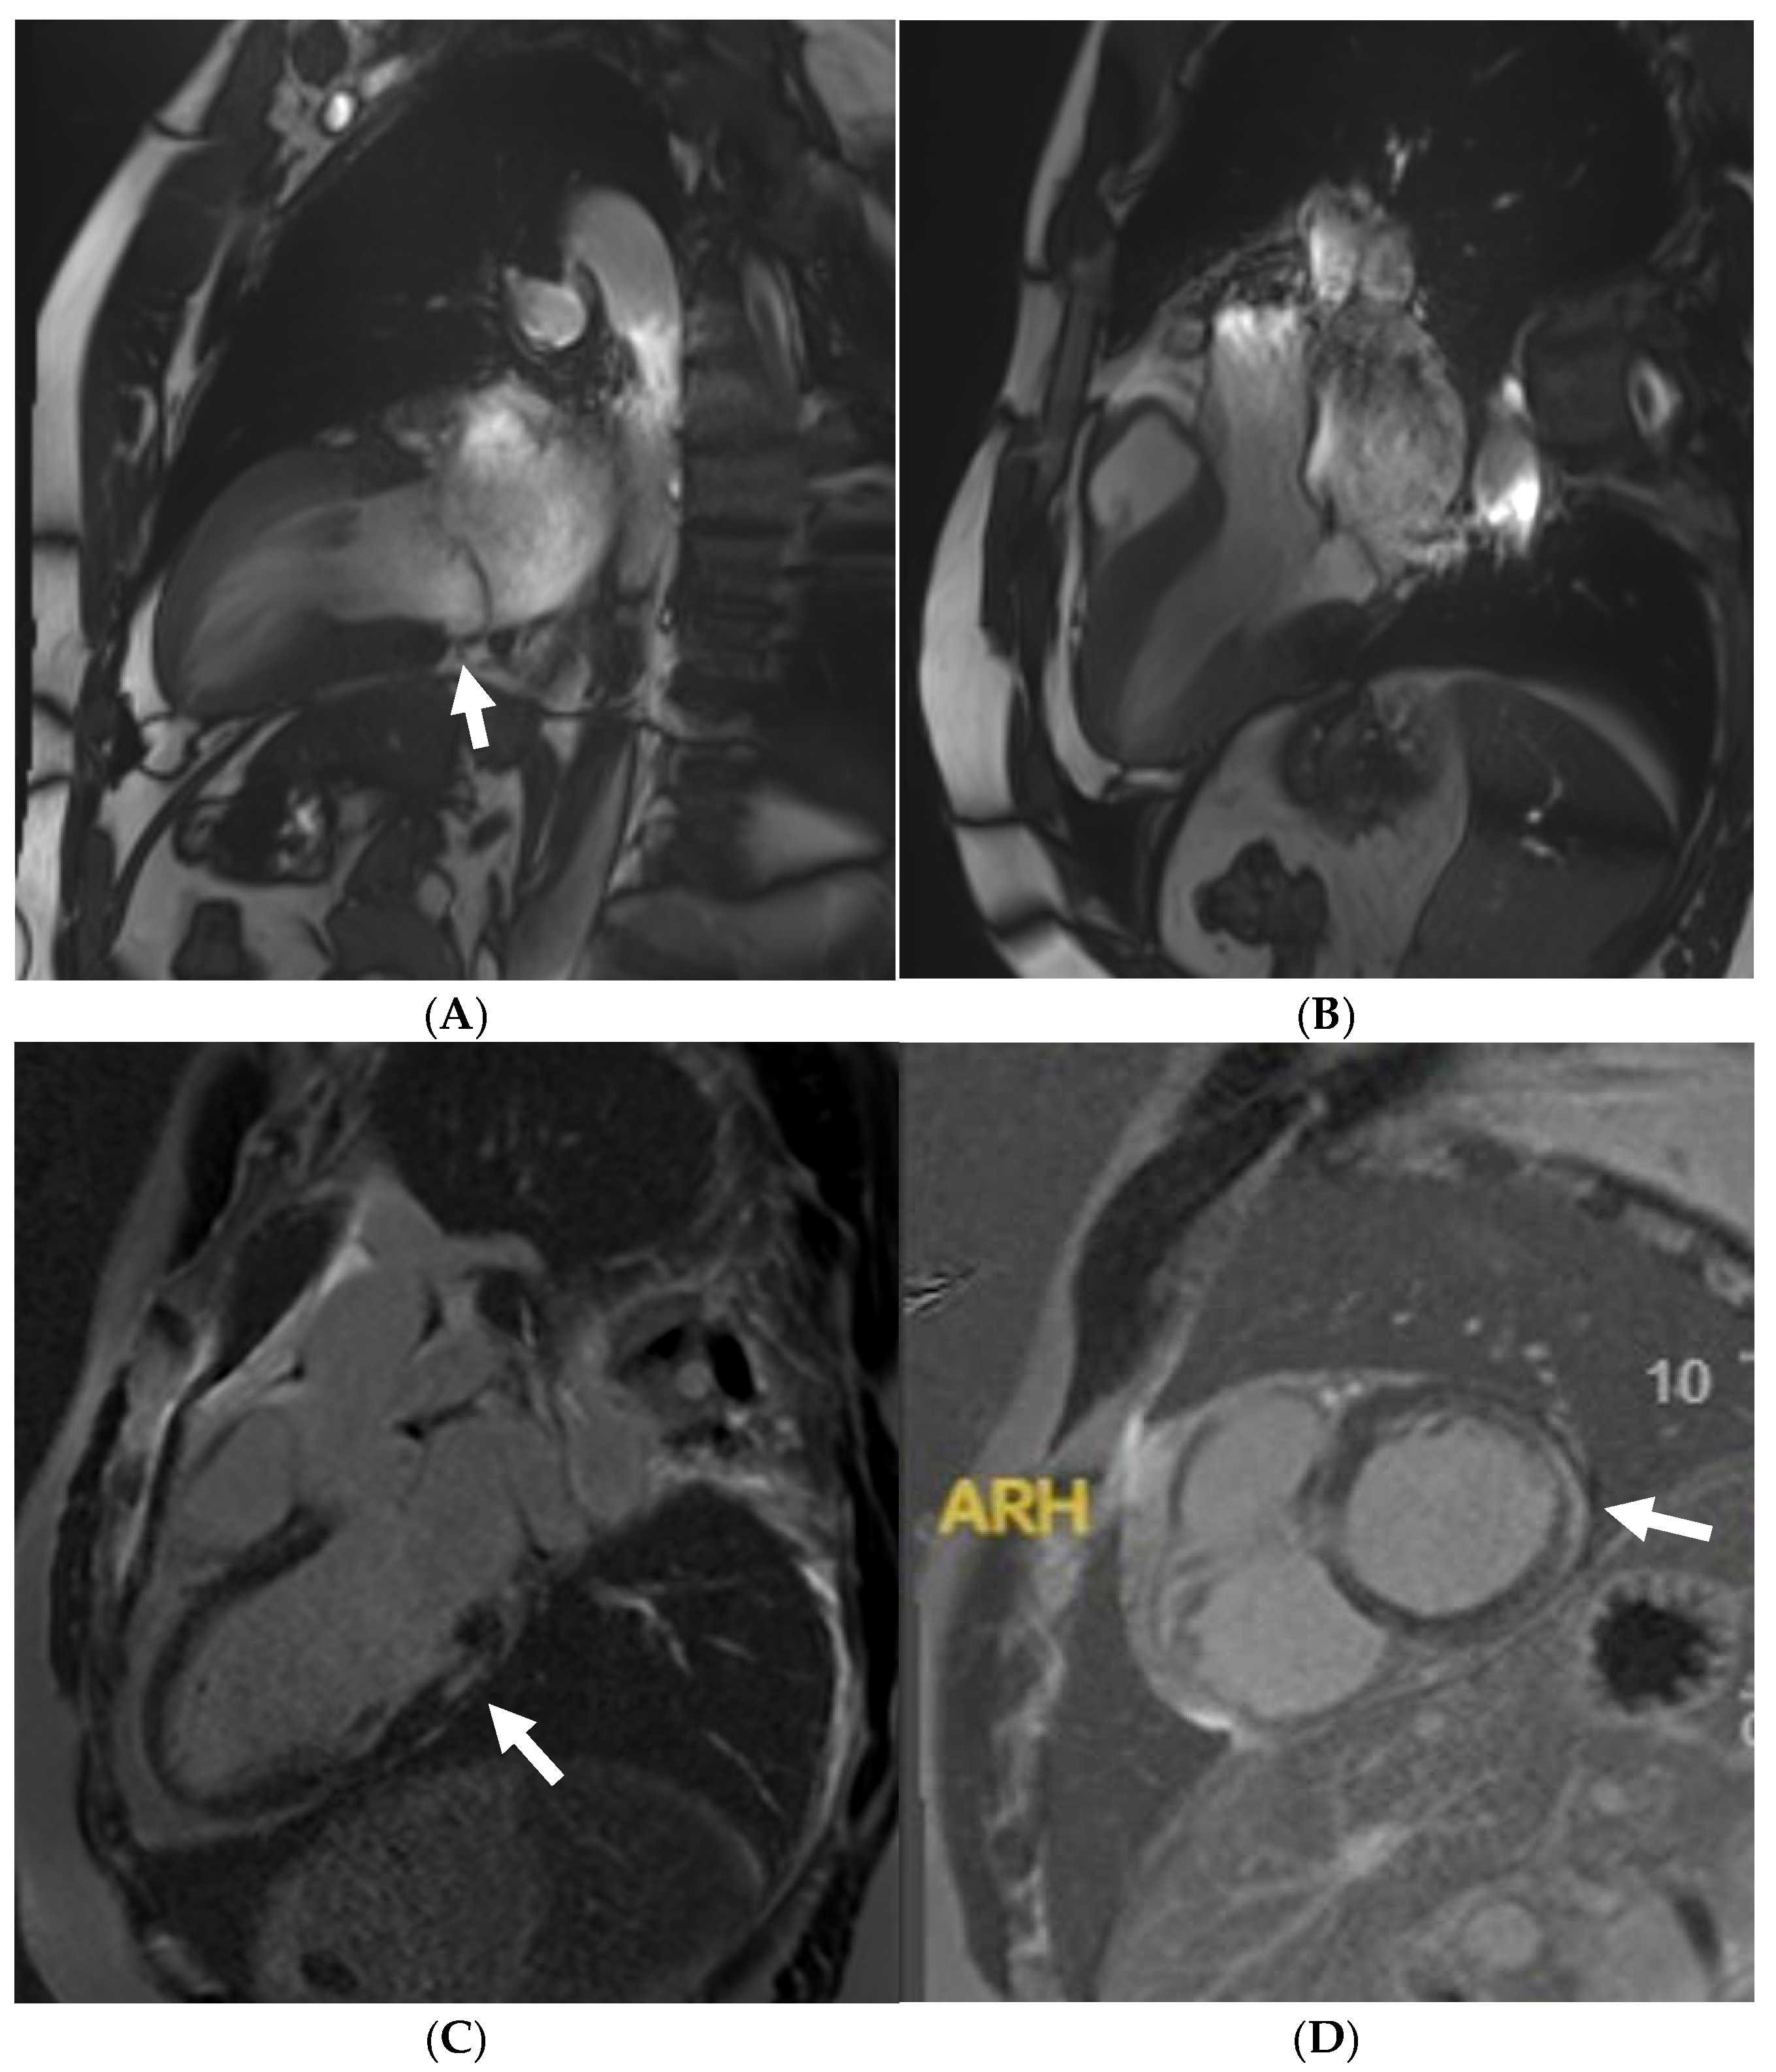

10. Arrhythmogenic Right Ventricular Cardiomyopathy